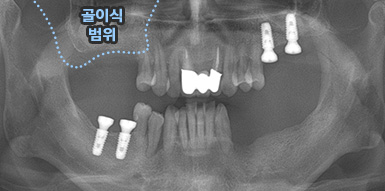

상악동 거상술

상악동 거상술 고난이도 뼈이식술 입니다.

청담네오플란트에서는 상악동 거상술을 비롯한

고난이도 임플란트 시술 노하우가 풍부한 치의학 박사

전문의가 직접 상악동 거상술을 시행합니다

상악동은 윗턱뼈 내부의 구조물로서 개개인에 따라 생김새가 다릅니다.

상악동의 바닥이 잇몸뼈 방향으로 많이 내려온 경우, 임플란트를 식립하기에

잇몸뼈가 부족하게 됩니다. 이러한 경우 상악동 내부로 뼈이식을 하는

상악동 거상술이 필요하게 됩니다.